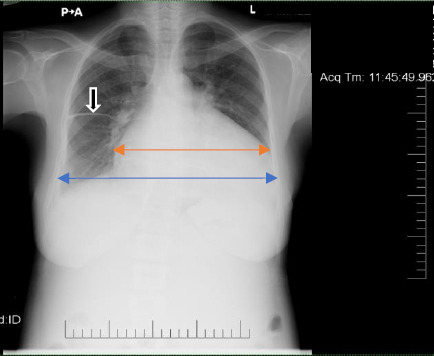

Cardiovascular diseases in pregnancy increase the risk of adverse maternal and foetal outcomes. Diagnosis and management of cardiovascular diseases, such as arrhythmias and heart failure in pregnancy, in resource-limited settings, is, however, challenging. We present a 31-year-old multiparous woman whose index presentation was for worsening symptoms of acute heart failure at 33 weeks of gestation. She had, however, had a prior history of breathlessness in a previous pregnancy for which she was diagnosed with peripartum cardiomyopathy. During this index clinical presentation, she was found to have dilated cardiac chambers with severe left ventricular systolic dysfunction and monomorphic ventricular tachycardia. Multidisciplinary team management resulted in successful cardioversion and satisfactory maternal and foetal outcomes.